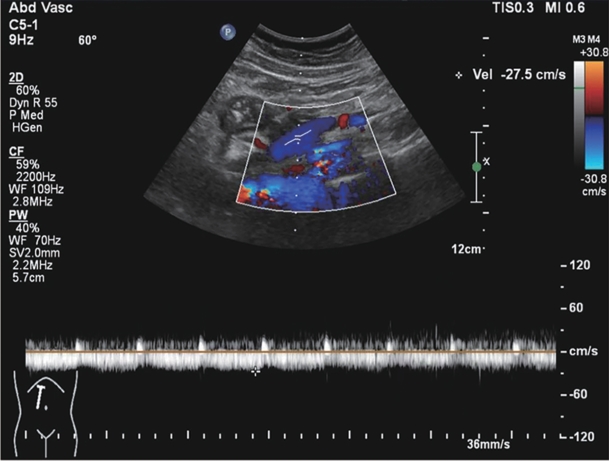

巨大自发性脾肾分流道栓塞联合抗凝治疗门静脉血栓1例报告

门静脉血栓是肝硬化患者常见且严重的并发症,门静脉血流动力学的改变与门静脉血栓的发生密切相关。合并巨大的自发性脾肾分流时门静脉灌注减少、血流速度减慢,极有可能削弱门静脉血栓的抗凝效果。本文将报道1例通过栓塞自发性脾肾分流道联合抗凝治疗策略,实现了门静脉的完全再通,然而,仍需高质量的临床研究进一步验证和支持这一策略的有效性。